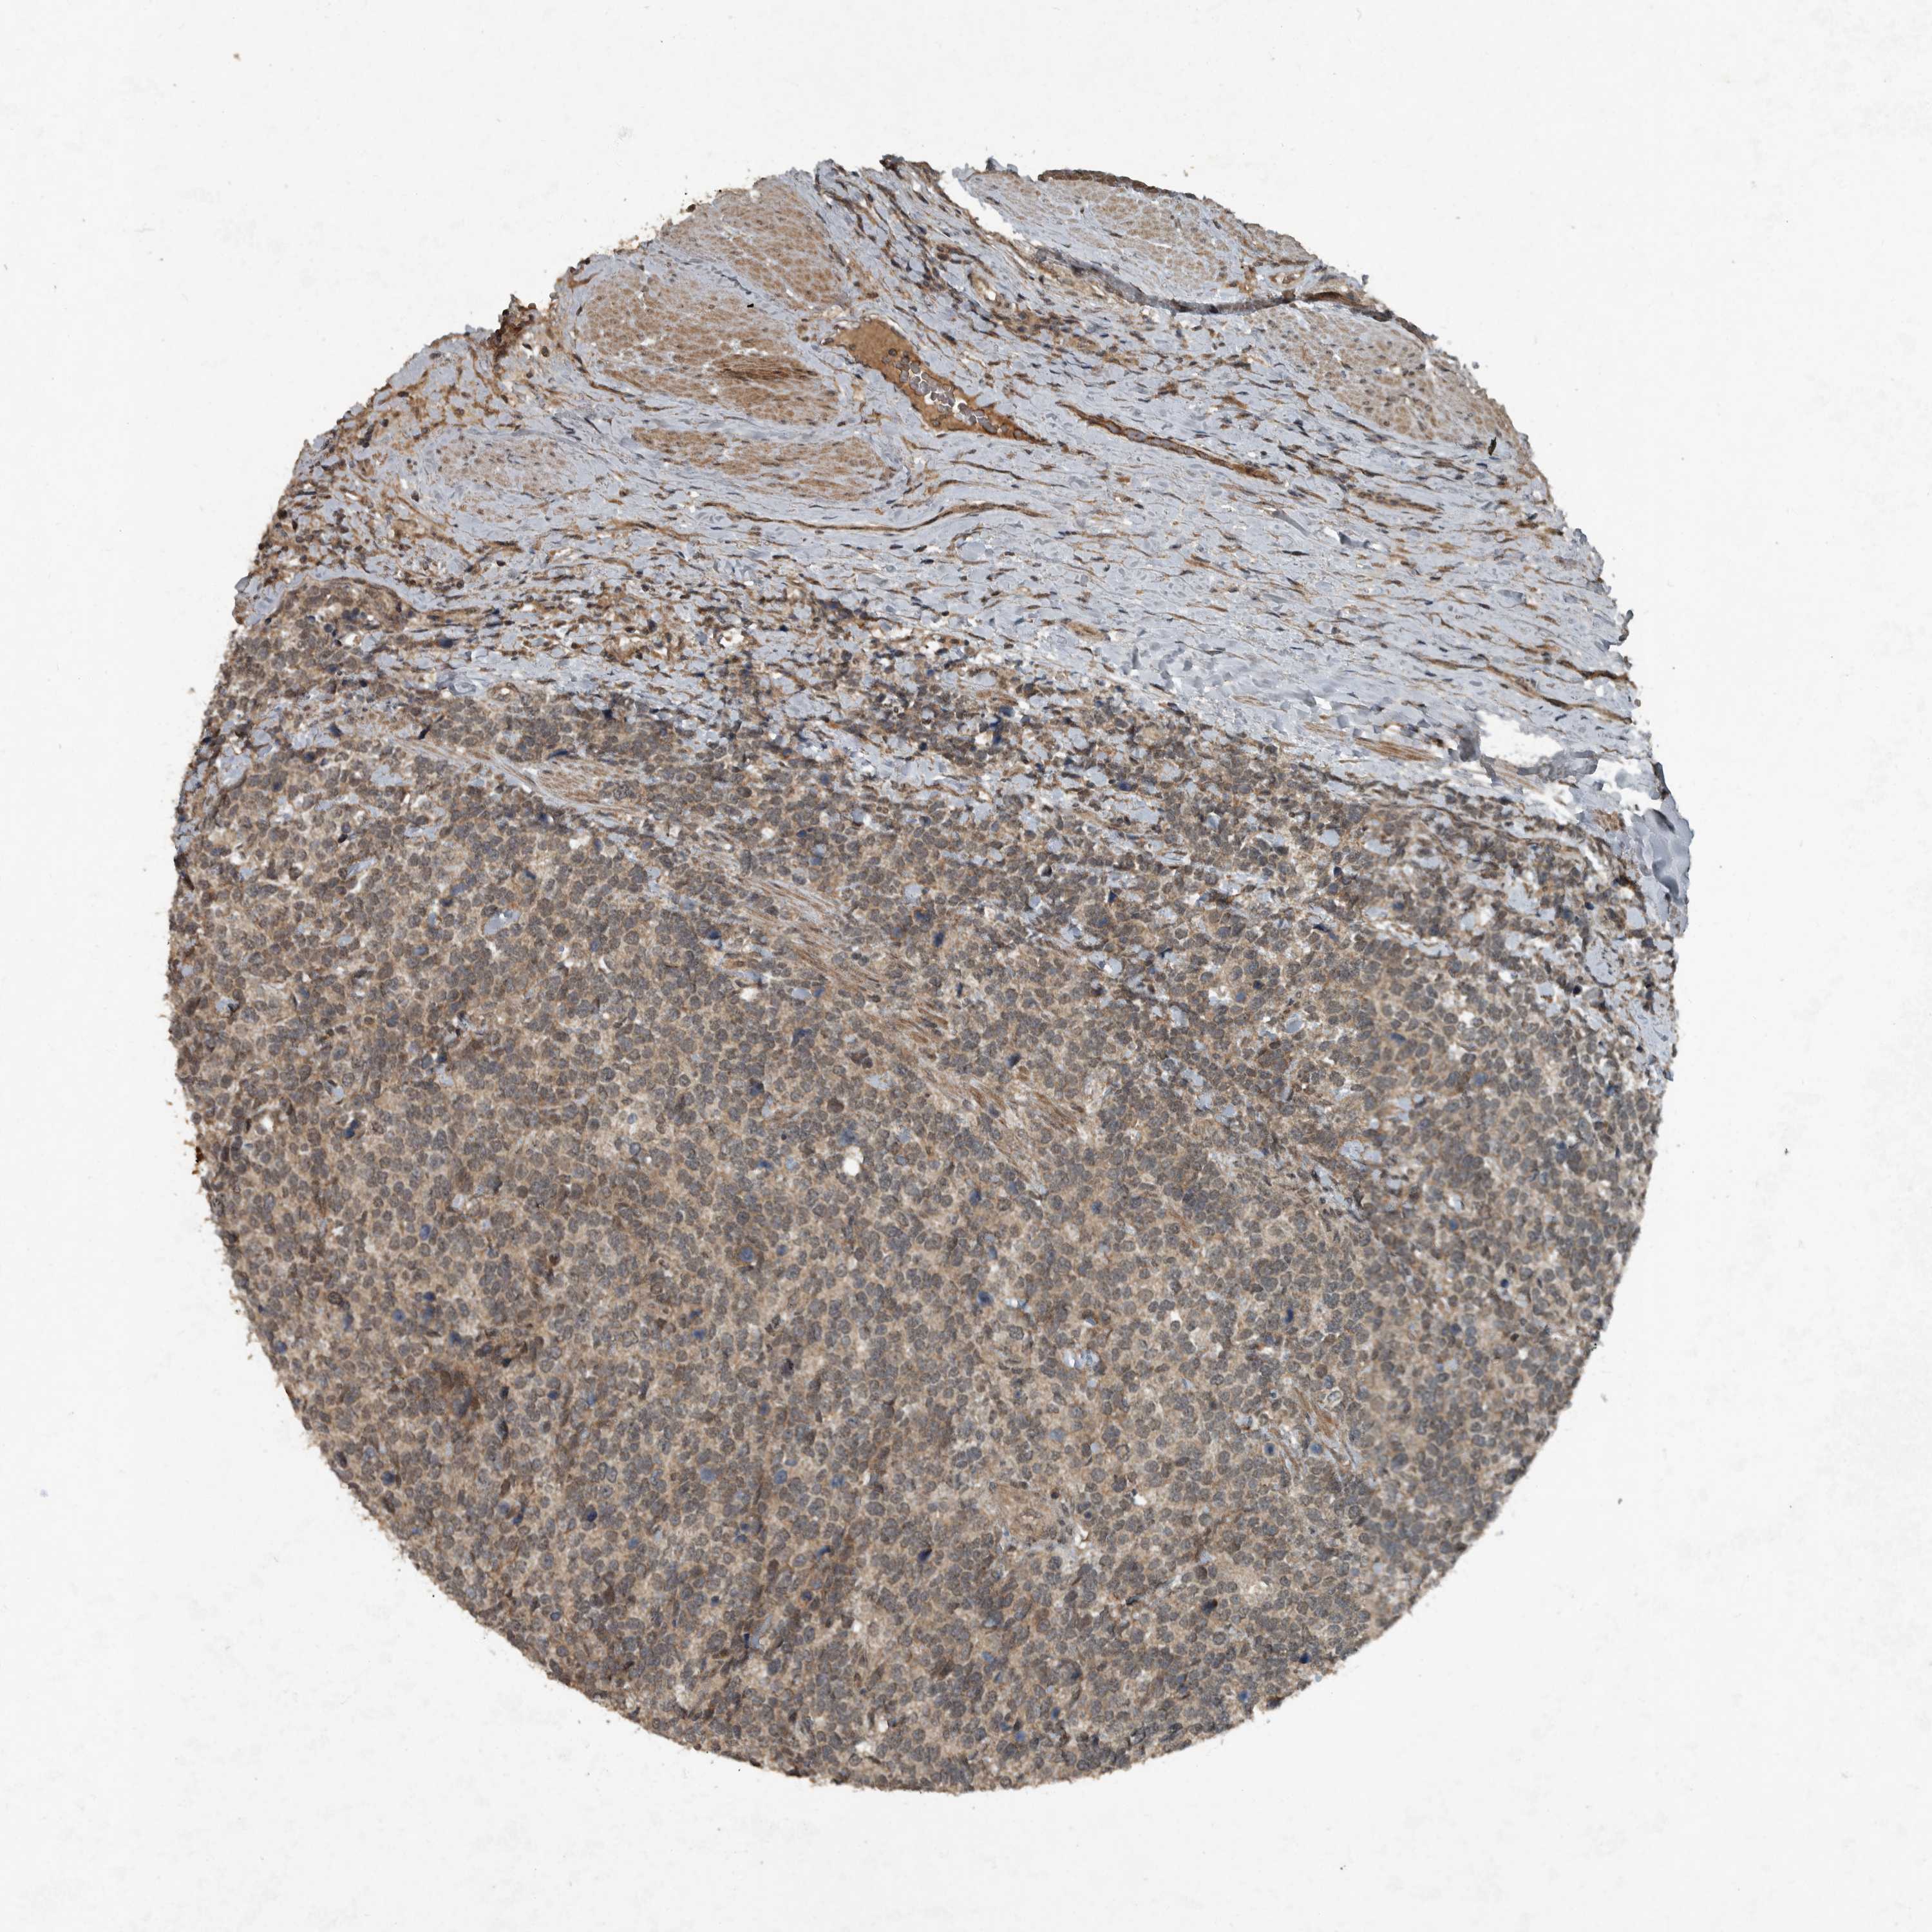

UROTHELIAL CANCER - Protein expressioni

A mouse-over function shows sample information and annotation data. Click on an image to view it in a full screen mode. Samples can be filtered based on level of antibody staining by selecting one or several of the following categories: high, medium, low and not detected. The assay and annotation is described here.

Note that samples used for immunohistochemistry by the Human Protein Atlas do not correspond to samples in the TCGA dataset.

Antibody stainingi

Antibody staining in the annotated cell types in the current human tissue is reported as not detected, low, medium, or high, based on conventional immunohistochemistry profiling in selected tissues. This score is based on the combination of the staining intensity and fraction of stained cells.

Each image is clickable and will lead to virtual microscopy that enables deeper exploration of all samples and also displays staining intensity scores, fraction scores and subcellular localization as well as patient and tissue information for each sample.

HPA001252

Urothelial carcinoma, High grade

Urothelial carcinoma, Low grade

Adenocarcinoma, NOS